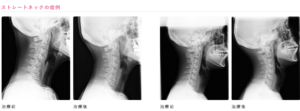

頚椎は、頭の下と肩の間にあって、全部で7個あります。ピンとこないと思うのでネットからレントゲン写真を見つけてきました。

下記の写真は、医療法人 良花会 整形外科とくはらクリニックさんから引用させていただきました。

頚椎は正常なら、7個の頸椎が、横から見ると緩やかに前に凸の状態で並んでいます。

それが、上記写真の1枚目と3枚目のように、一直線になったのがストレートネックです。